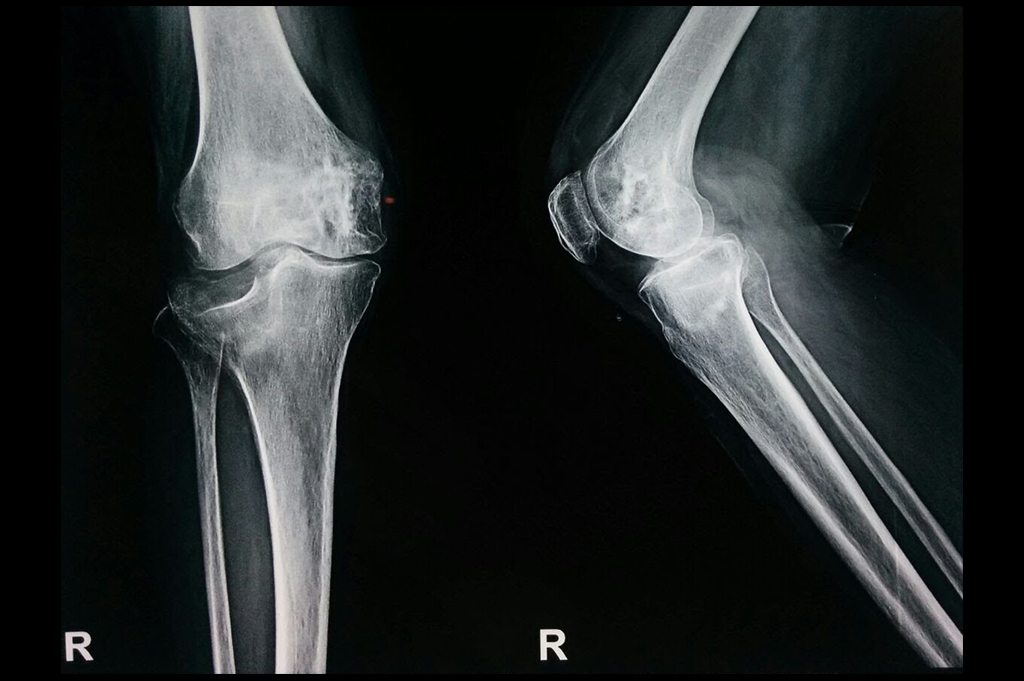

Osteoarthritis – High Tibial Osteotomy - HTO